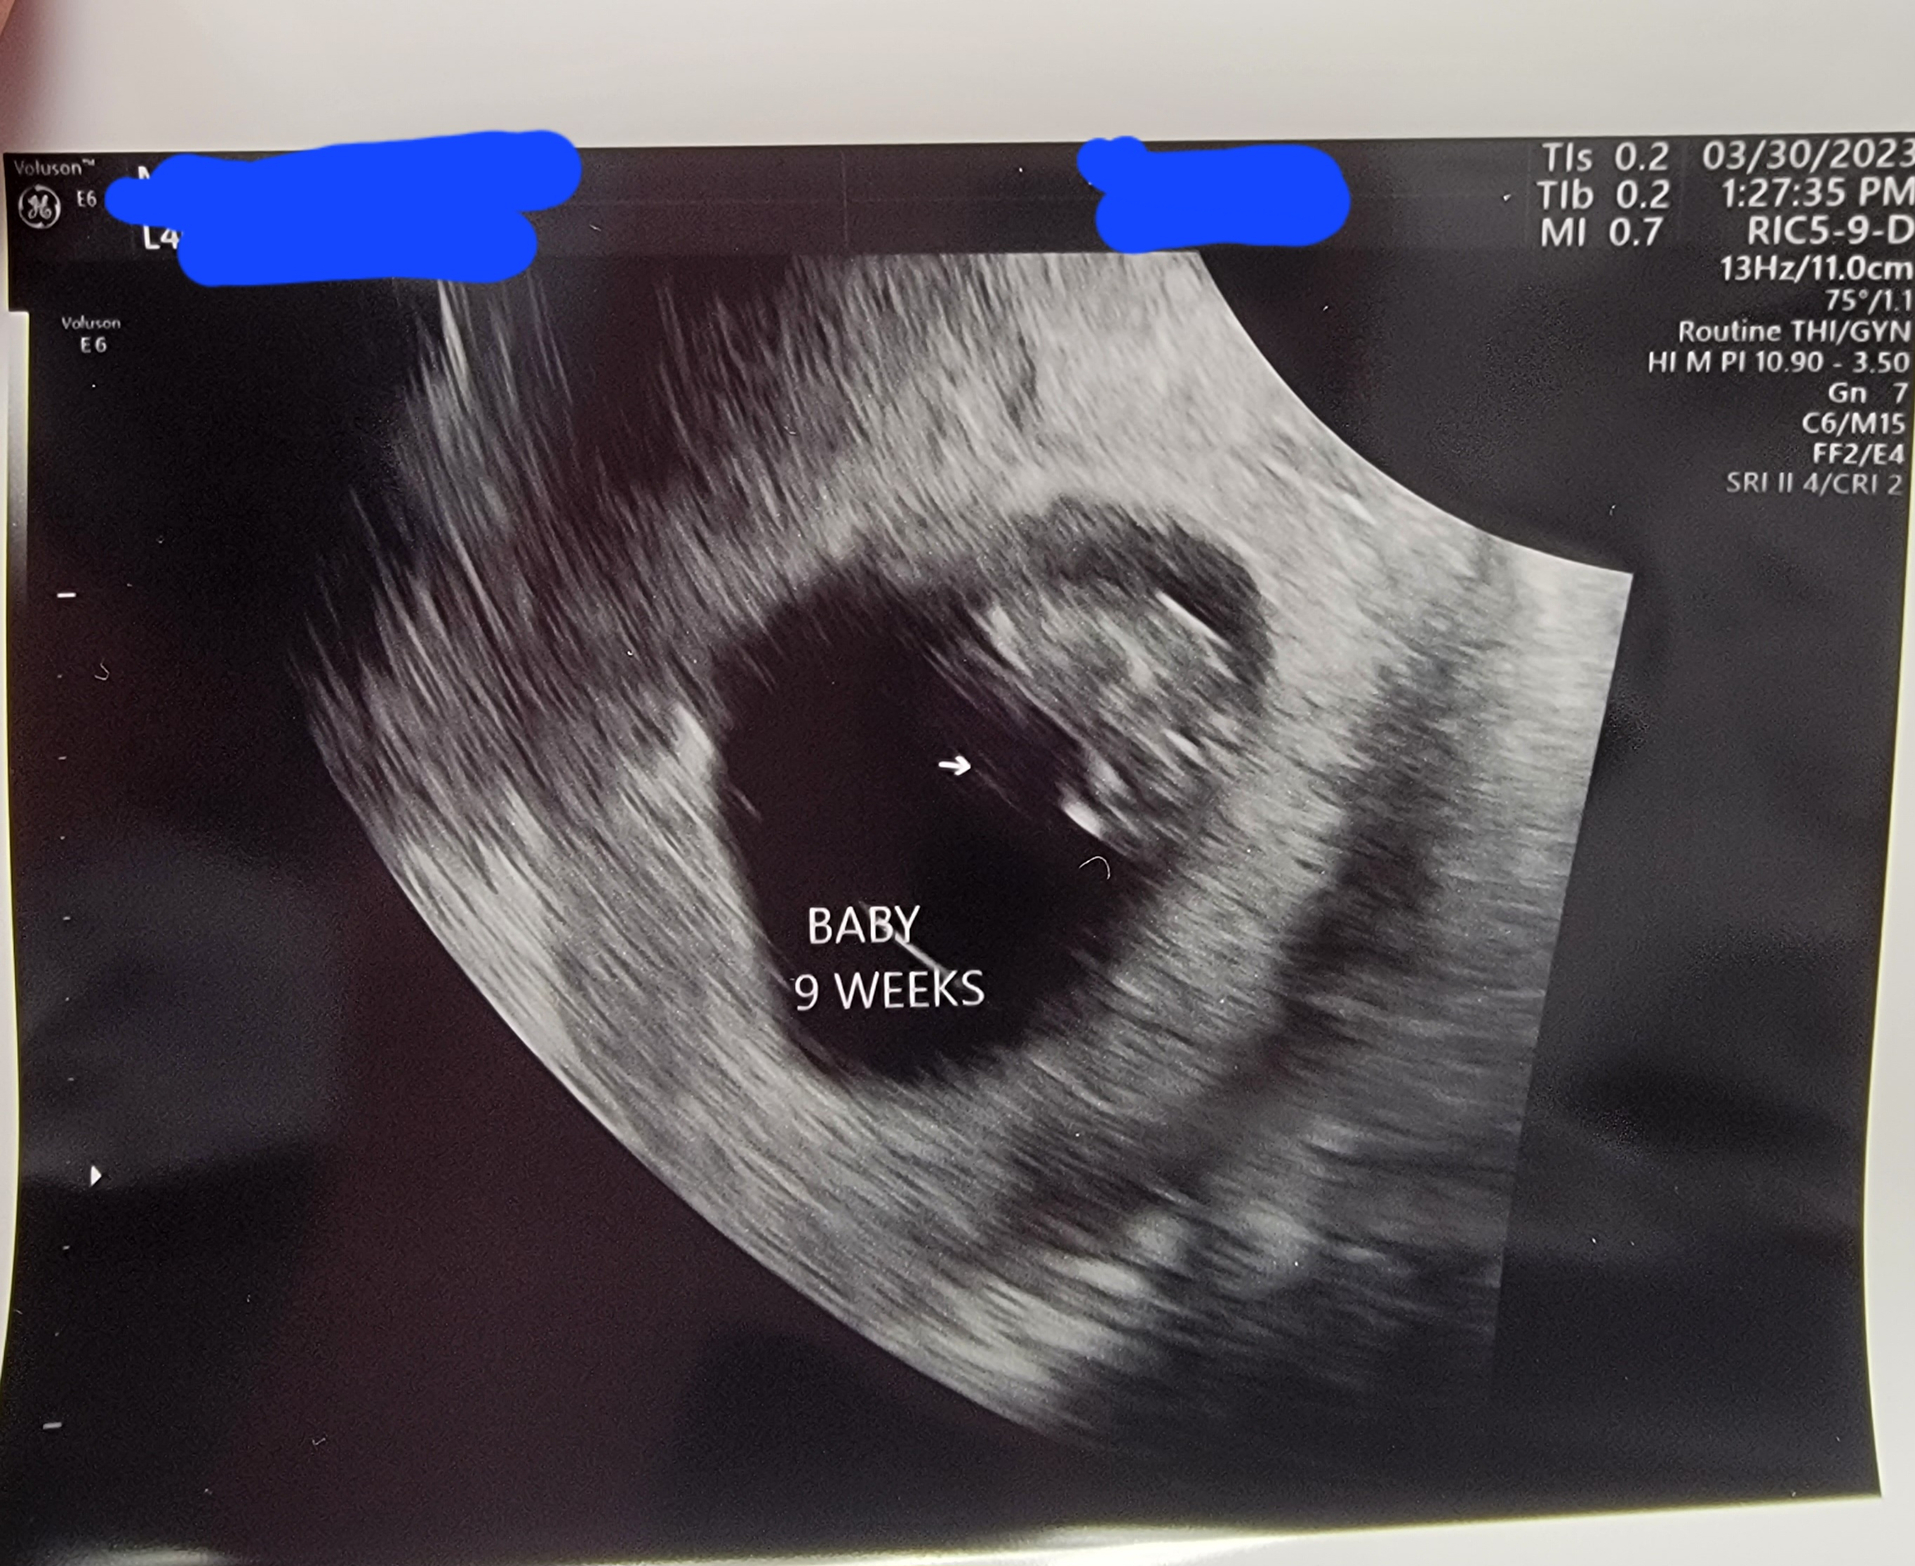

Got to see little bb for the first time today and hear their heartbeat. That was sooo cool. I'm so glad they are doing well in there. Measuring right on target for a Nov 4th due date. Heartrate was 157bpm.